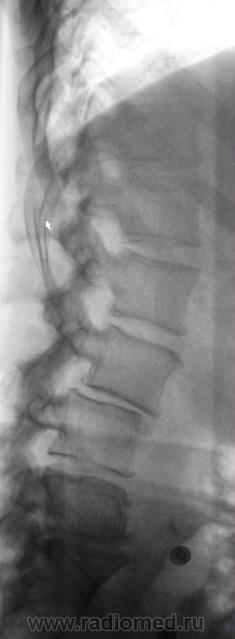

Пациент направлен в рентгеновский кабинет врачом невропатологом для рентгенографии поясничного отдела позвоночника. Пациент отмечает, что в течение последних 3 лет, его беспокоят боли в пояснице и в тазобедренных суставах. Произведена рентгенографии поясничного отдела позвоночника в ортоположении.

- как такого поясничного лордоза нет;

- выраженный субхондральный склероз смежных замыкательных пластинок на уровне L2-L3, L3-L4, L4-L5,L5-S1;

- снижение высоты межпозвонковых дисков на уровне  L2-L3, L3-L4, L4-L5, значительное L5-S1(фиброзный анкилоз);

- тело поясничного позвонка L5, несколько деформировано, значительно склерозировано;

- смещение тела поясничного повонка L3 кпереди на 3-4мм;

- деформирующий спондилоартроз межпозвонковых суставов;

Остеохондроз  L2-L3, L3-L4, L4-L5(антелистез L3) 2 период, L5-S1 4 период( клас.по Осна)

///как такого поясничного лордоза нет/// Я бы даже добавил, угловой кифоз в L4-L5 позв. сегменте.

Травмы в анамнезе нет. Возраст - 47 лет. Хотя всю жизнь, этот пациент работал "тяжело и весьма".